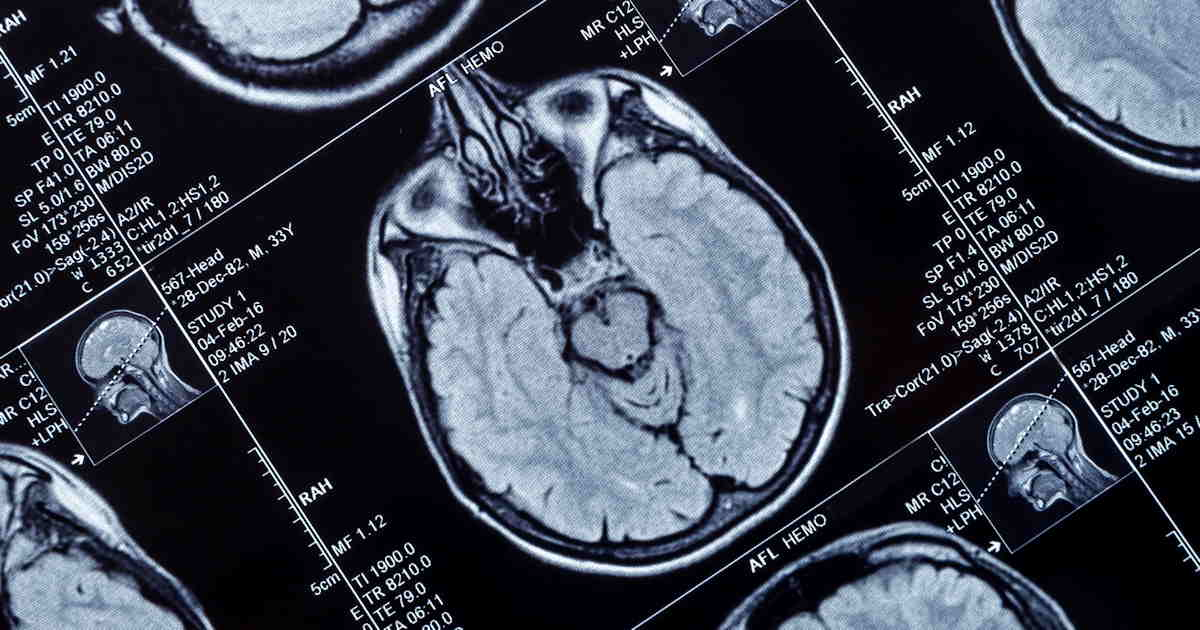

Researchers led by Catarina Tristao-Pereira, of the Spanish National Center for Cardiovascular Research in Madrid, studied F-18 FDG-PET scans of individuals with subclinical atherosclerosis. Over a five-year period, these high-risk individuals had a steeper decline in cerebral glucose metabolism compared with individuals at low risk.

Participants underwent cerebral F-18 FDG-PET baseline scans and then during follow-up visits over five years, with annual percentage changes in FDG brain uptake assessed as the primary outcome. Sixty-one (16%) participants were women and 309 (84%) were men, while 73 (20%) participants were apolipoprotein E (APOE) e4 carriers susceptible for Alzheimer's disease.

According to the analysis, a persistent high risk of cardiovascular disease was associated with an accelerated decline of cortical F-18 FDG uptake compared with low-risk individuals. Specifically, on average, standard uptake value ratios (SUVRs) decreased by 61% per year in the whole cortex and by 77% per year in hypometabolic regions associated with Alzheimer's disease.